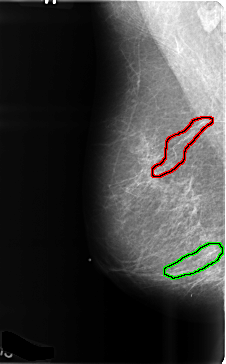

B_3470_1.RIGHT_MLO

FILE: B_3470_1.RIGHT_MLO.OVERLAY

TOTAL_ABNORMALITIES 2

ABNORMALITY 1

LESION_TYPE CALCIFICATION TYPE VASCULAR DISTRIBUTION N/A

ASSESSMENT 2

SUBTLETY 5

PATHOLOGY BENIGN_WITHOUT_CALLBACK

TOTAL_OUTLINES 1

BOUNDARY

ABNORMALITY 2